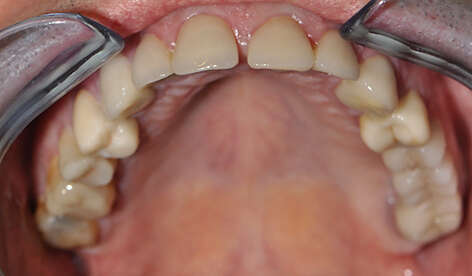

2. Eclaircissment et couronnes céramo-céramiques.